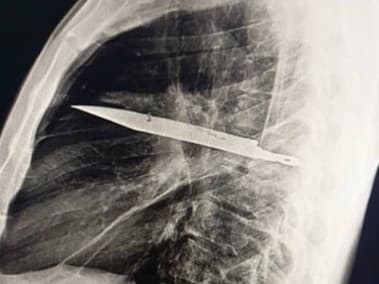

TANZÁNIA - Lekári v Tanzánii neverili vlastným očiam, keď zistili, že 44-ročný muž mal v tele celé roky zapichnutú čepeľ noža. Pacient pritom nepociťoval žiadne vážnejšie ťažkosti a sám uviedol, že žil „bez problémov“. Na prípad upozornil odborný časopis Journal of Surgical Case Reports.

Štyridsaťštyriročný muž prišiel do nemocnice a sťažoval sa na vytekajúci hnis pod pravou bradavkou. Neudával žiadnu bolesť na hrudníka, ani ťažkosti s dýchaním, kašeľ, či horúčku a jeho vitálne funkcie boli v norme, informoval portál Need to Know.

Lekári si nevedeli vysvetliť príčinu jeho problému až do chvíle, kým si pacient nespomenul na udalosť, ktorá sa mu stala pred ôsmymi rokmi. Vtedy utrpel počas „násilnej potýčky“ viaceré rezné rany na tvári, chrbte, hrudníku a bruchu a ošetrovali ho lekári. Podľa pacienta prebiehal od tejto udalosti  jeho život „bez problémov“, až kým si nevšimol hnis vytekajúci spod bradavky. Až röntgenové vyšetrenie odhalilo šokujúcu príčinu – veľkú čepeľ noža uviaznutú v oblasti hrudníka, ktorý prenikol do tela pacienta cez pravú lopatku.

Našťastie sa vyhol všetkým hlavným orgánom. Lekári mu predmet chirurgicky odstránili a zároveň mu odsali hnis vytvorený odumretým tkanivom. Muž zostal na jednotke intenzívnej starostlivosti 24 hodín v Národnej nemocnici Muhimbili v Tanzánii a potom ho previezli na bežné oddelenie, kde strávil ďalších desať dní pod dohľadom lekárov.  Následné kontroly prebehli „bez komplikácií“.